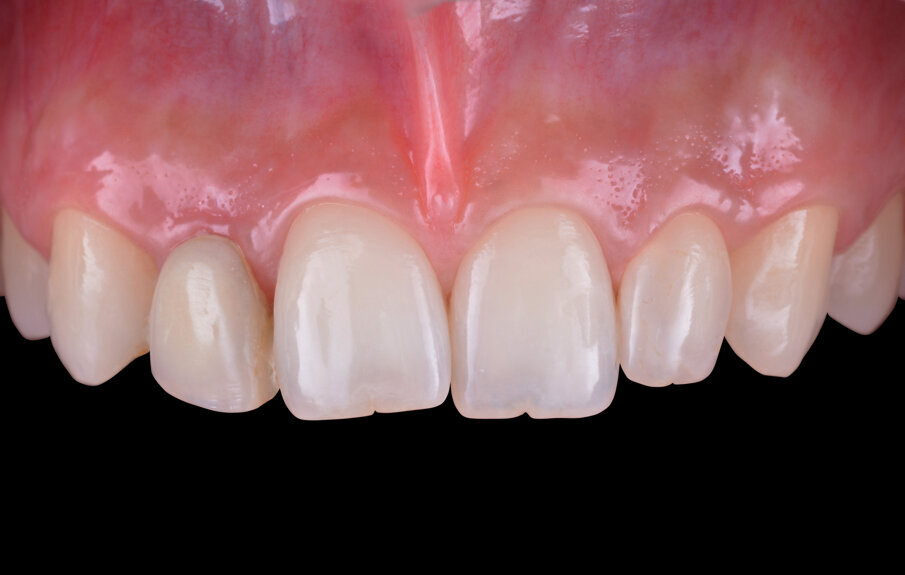

Le successive fasi protesiche provvisorie consistono nel modellare la regione cervicale della corona al fine di ottenere un condizionamento dei tessuti molli che ottengano, durante la maturazione, una festonatura simile a quella dell’elemento omologo controlaterale e un buon mimetismo radicolare in visione laterale. Giunti a questo punto della terapia, la paziente richiede anche la correzione della recidiva ortodontica che caratterizza gli incisivi centrali superiori, valutando il riallineamento dell’elemento dentario 1.1 che risulta mesioverso e lievemente sovrastante il versante mesiale dell’elemento 2.1. Dopo uno studio ortodontico del caso, si propone una terapia ortodontica con degli allineatori trasparenti che, in pochi mesi, corregge il mal posizionamento dentario soddisfacendo le richieste estetiche della paziente. Valutata clinicamente e radiograficamente la salute e la stabilità dei tessuti duri e molli fino a questo punto trattati (Fig. 13), si procede con le fasi di protesizzazione definitiva. L’impronta definitiva è rilevata seguendo il protocollo digitale e utilizzando lo scanner intraorale Trios 3Shape (Figg. 14, 15).

Fig. 13 - Maturazione dei tessuti molli dopo il condizionamento per mezzo di un provvisorio avvitato.